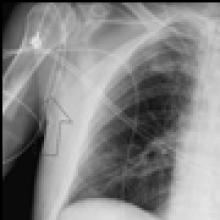

Figure 3. Postoperative chest radiograph after VATS decortication, with left pleural drainage tubes in place.

The chest tubes are maintained on suction to make sure there is complete lung expansion and adequate drainage of the pleural space (Figure 3). Once the drainage is less than 200cc/24hrs the tubes can be removed. For patients with an empyema, intravenous antibiotics are continued during the postoperative course and for a further 14 days of oral antibiotics once the patient is discharged. For patients with hemothorax, antibiotics are continued postoperatively for 48 hours.